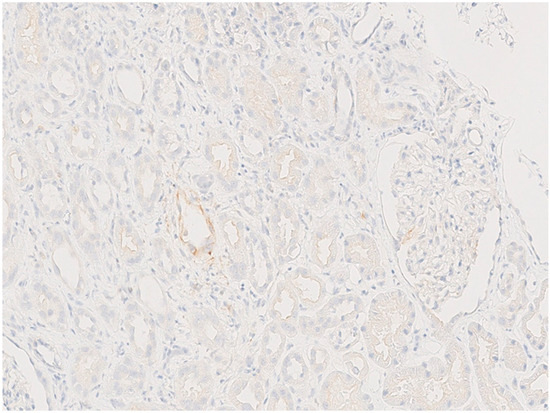

The patient developed nephrotoxicity after the second cycle, for which renal biopsy was performed. Renal biopsies showed no glomerular proliferative lesions, and electron microscopy did not reveal any electron-dense deposits. Severe tubular damage, characterized by the loss of the brush border, flattening of the epithelium, vacuolization, and tubular distalization with focal tubular necrosis were present together with signs of tubular regeneration such as cariomegalia and mild atypia. The underlying chronic renal damage was mild to moderate, with interstitial fibrosis and tubular atrophy not exceeding 10%. No significative lymphocyte infiltration was observed, and the immunohistochemical assessment of PDL-1 was negative. It was noteworthy that the antibody anti-p53 showed a patchy moderate-to-strong staining of the nuclei of proximal renal tubules (Figure 1, Figure 2, Figure 3 and Figure 4).

A thorough morphological examination including electron microscopy can assist a nephropathologist in distinguishing between ATN and AIN lesions with greater precision. However, both drugs can cause both pathological patterns, making it necessary to use advanced immunohistochemical techniques to determine which drug is responsible for the nephrotoxicity. In our case, the tubular expression of anti-PD1 was negative, while the tubular expression of p53 was positive.

Histological tubular expression with anti-PD1 is an experimental technique in nephrology. Cassol et al. [24] published a case series that tested its use on PD1-induced AIN. In the study conducted by Cassol, only monotherapies using checkpoint inhibitor drugs were administered to patients. Among those who received anti-PD-1 therapy and were diagnosed with AIN based on renal biopsy samples, PD-L1 staining was found to be positive not only in inflammatory cells but also in tubular epithelial cells. If PD-L1 staining is negative or is observed only in inflammatory cells within fibrotic areas, then it is likely that the AIN is associated with causes other than anti-PD-1 therapy.

Our group also utilized this technique to customize the diagnosis and treatment of anti-PD1-induced AIN, and the results were in line with those of Cassol [25]. By identifying PDL1-negative tubular damage in our patient, we were able to demonstrate that the damage was caused by platinum and not pembrolizumab-mediated.

Figure 3. Weak and focal tubular decoration of PDL-1; the interstitial space appears free of inflammatory infiltrate.